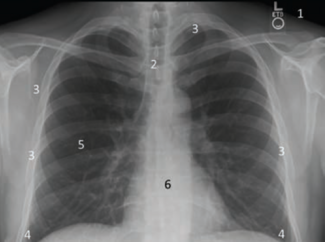

A critical part of a cardiology consultation and review in preparation for a cardiac catheterization should include the chest x-ray (CXR). How should we approach reading the CXR?